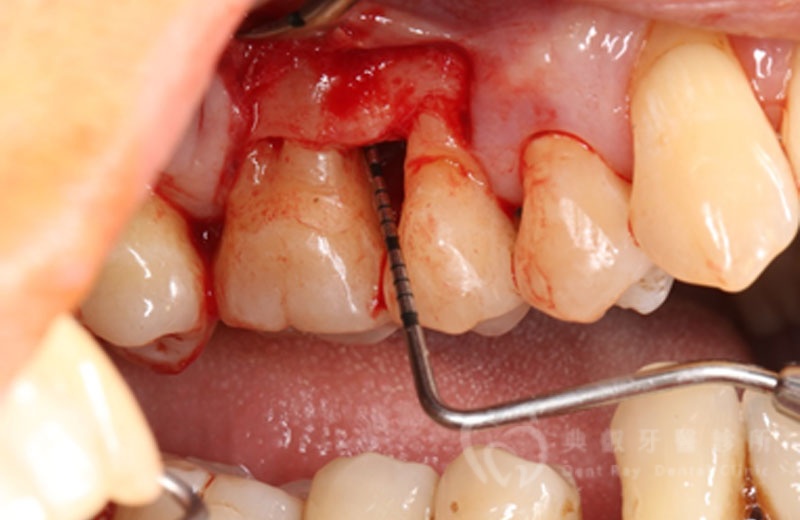

牙周手術案例三

術後六個月